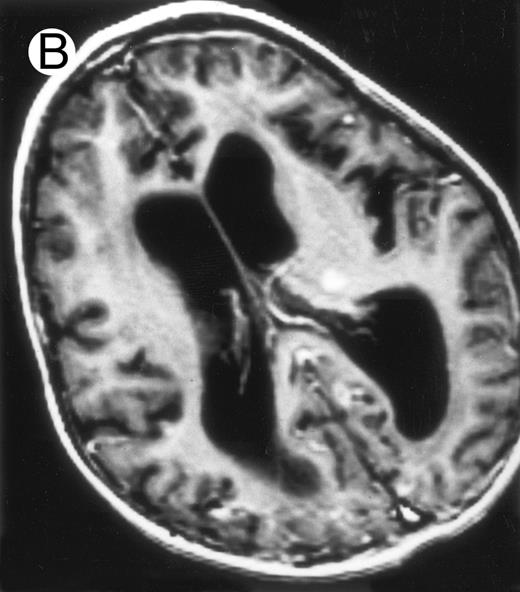

Three different aspects of brain imaging in HLH patients. (A) CT scan of a 3-month-old baby showing a large subdural effusion, several necrotic areas and hypodensities of the white matter. (B) Brain magnetic resonance of a 14-month-old boy showing large confluent areas of hypersignal in T2-weighted images. (C) Large symmetrical necrotic areas of cerebellar white matter in a 41/2-year-old girl (MRI).

Among the nine children with initial neurological symptoms, seizures were the most frequent initial symptom in the youngest patients, whereas ataxia was found in the two oldest patients (46 and 58 months old, respectively) (Table 1). All nine patients had the same CSF abnormalities as patients with meningitis only. Eight of these nine patients had a neuroradiological study performed at the time of their first neurological symptoms (Table 1). The two most frequent lesions were focal necrosis with parenchymal volume loss and atrophy (Fig 2A and C) and white matter abnormalities (Fig 2B). Several small focal lesions with hypersignal at MR imaging that enhanced after administration of gadopentate dimeglumine (or contrast on CT scan) were also observed in two cases.

Abnormalities on brain imaging appeared to roughly parallel the severity of clinical manifestations. All patients with neurological symptoms, but also half of the patients with initial meningitis, had abnormal brain imaging usually consisting of a combination of diffuse white matter abnormalities and necrotic areas with parenchymal volume loss, as previously described.8,23 In patients with isolated meningitis, however, only white matter abnormalities were detected, whereas necrotic lesions and cerebral atrophy were found in patients with neurological symptoms. These lesions progressed despite chemotherapy. Previous neuropathological studies have demonstrated infiltration by monocytes and activated lymphocytes of leptomeninges and brain parenchyma along penetrating vessels.24,25 Infiltration is associated with focal and confluent areas of myelin pallor, as well as neuronal loss, tissue necrosis, and cavitation,24,25 findings that were also demonstrated in the neuropathologic study of five patients in our series. Leukocytes infiltrating the CNS probably secrete cytokines and other neurotoxic factors, such as tumor necrosis factor-α (TNF-α), which may be responsible for the myelinic alteration observed in neurologically asymptomatic patients. Infiltrating leukocytes could also activate in parallel the numerous resident brain macrophages (the microglial cells) and astrocytes, which in turn, can secrete neurotoxic glutamate and free radicals.26